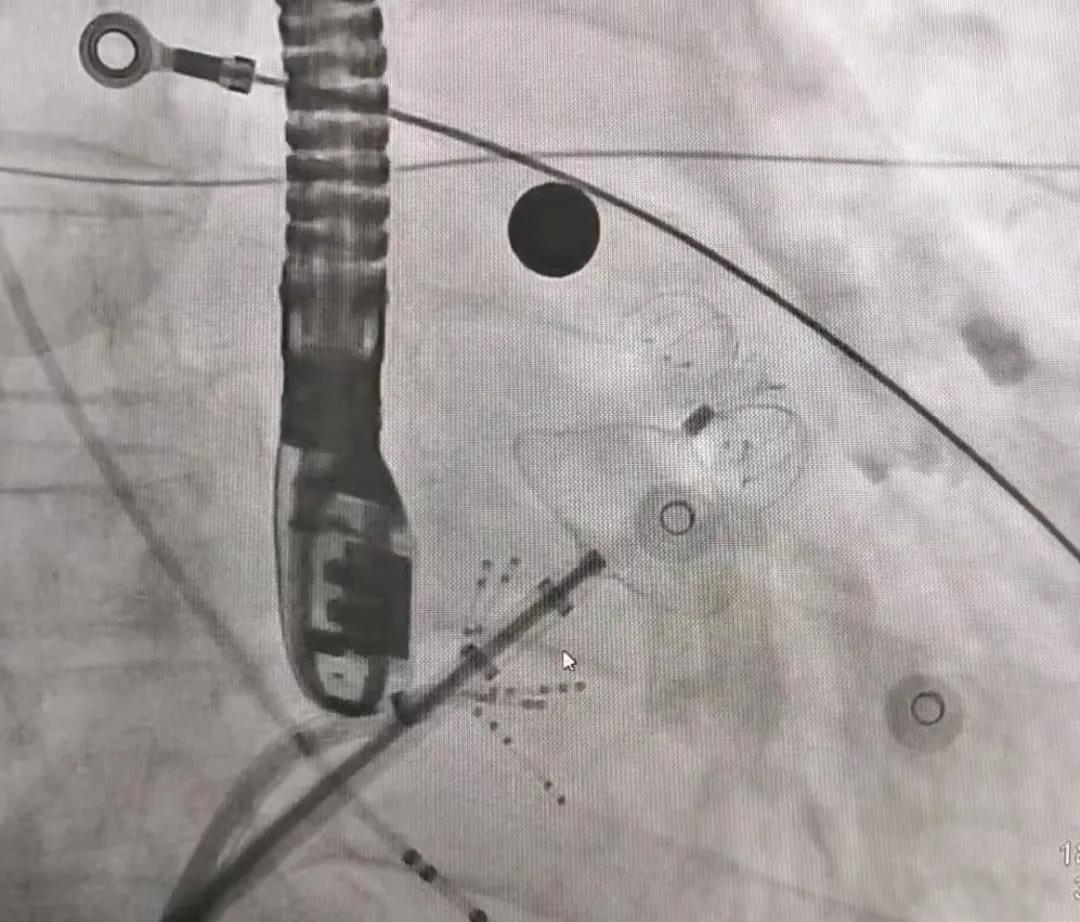

武汉亚心医院黄克强医生首先针对三个病例进行了基本情况介绍,让学员参与术前方案制定,随后观摩并参与整个手术过程。随后,苏晞院长带领学员完成了两例鸡翅型左心耳及一例风向标型左心耳的封堵,让参与学员在实际情况中对不同的左心耳封堵方案进行讨论和验证,并切实感受使用LAmbre™左心耳封堵器带来的更佳手术体验。

患者男,63岁,间断心悸病史11年。术前TEE显示左心耳无血栓,拟行房颤射频消融联合左心耳封堵术。左心耳测量锚定区约为27mm,封堵区约为25mm,选用LAmbre™2632封堵器进行封堵,达到了理想的封堵效果。LAmbre™独特的锚定机制能确保左心耳封堵器稳定牢固,牵拉测试十分稳定,符合COST原则,随后释放封堵器。